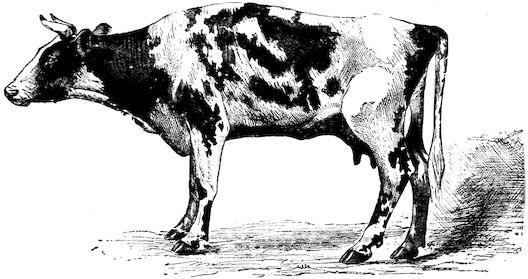

Fig. 2.—Horse suffering from osseous cachexia.

Fig. 3.—Pig suffering from osseous cachexia (fourth stage).

Fig. 4.—Deformity of the face in the horse shown in Fig. 2.

Fig. 5.—Head of a pig suffering from osseous cachexia.

Fig. 6.—Osseous cachexia. This condition developed in two months, the last month of gestation and the first of lactation.

Fig. 7.—Osseous cachexia: softening of the maxillæ.

Fig. 8.—Transverse section through the middle region of the face in a pig suffering from osseous cachexia.